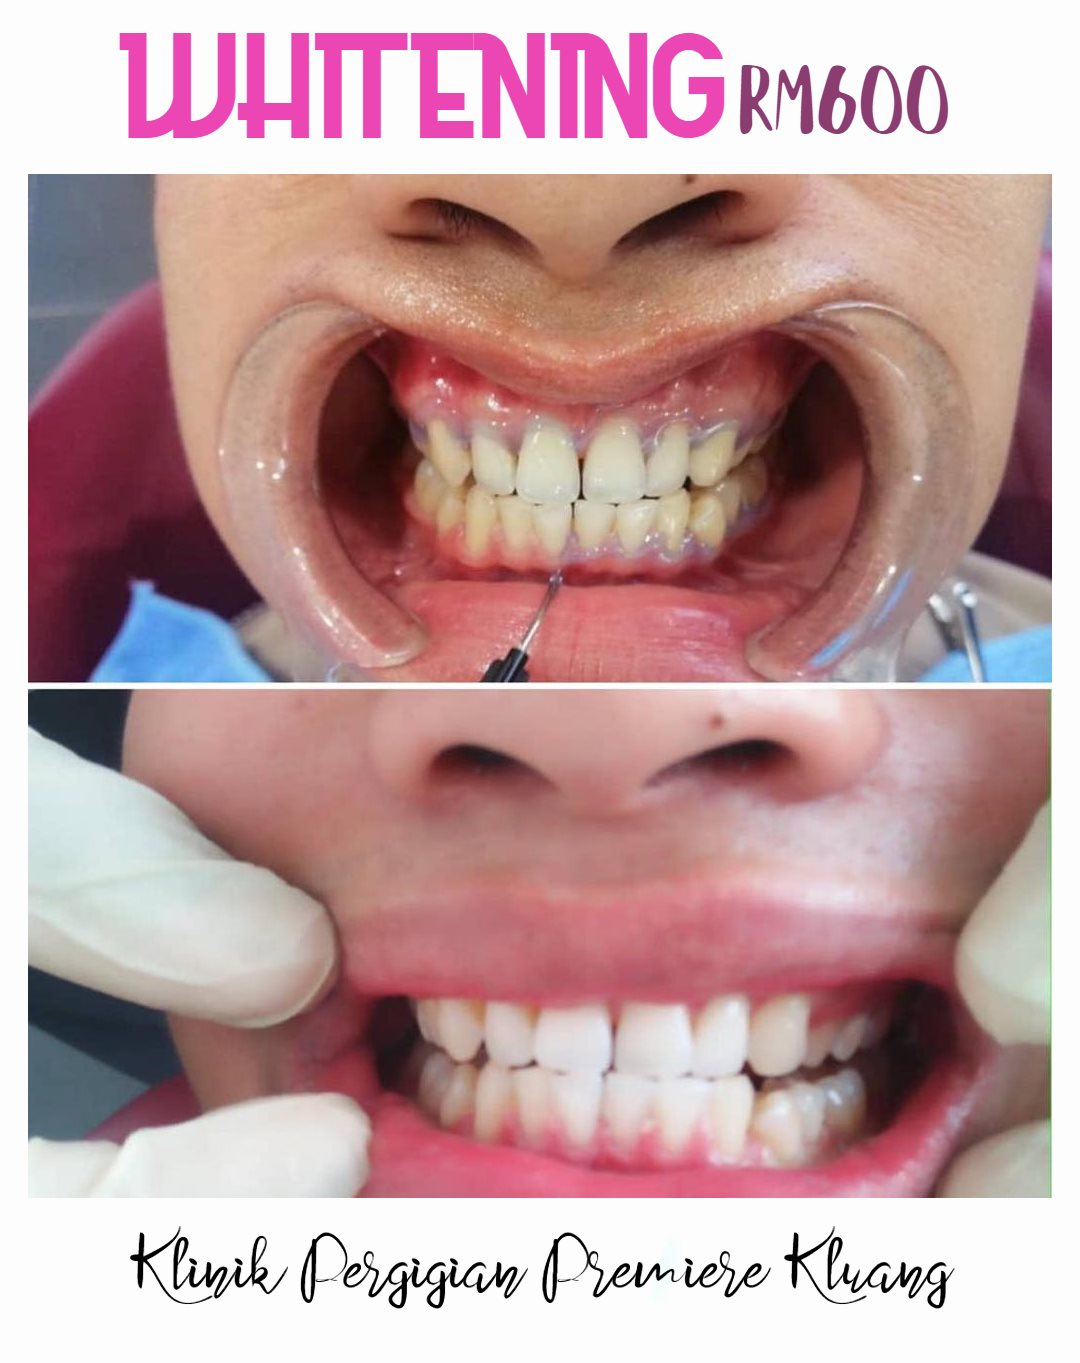

#klinikpergigianpremiere #premierekluang #klinikgigikluang #kluang #braceskluang #clearaligner #orthodontic #teethwhitening #pemutihangigi #compositeveneer #veneer #crown #bridge #rootcanaltreatment